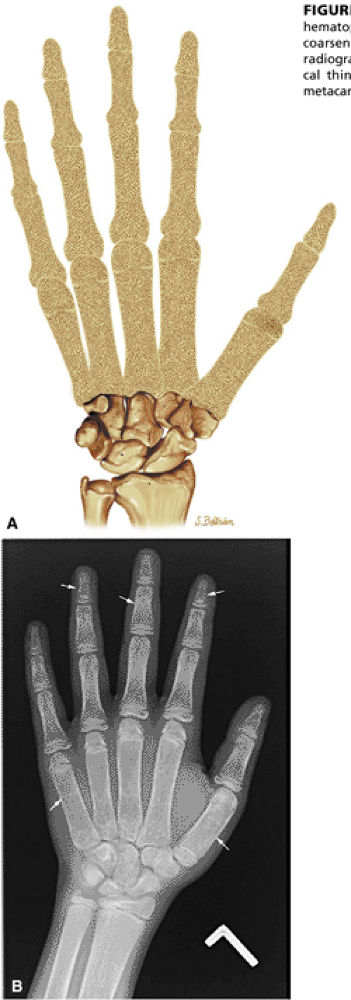

FIGURE 13.86 ● Expansion of marrow spaces due to increased demand in hematopoiesis. (A) Coronal graphic illustration shows expansion of marrow spaces with coarsened trabeculae and cortical thinning involving the digits. (B) Anteroposterior radiograph of the hand shows generalized osteopenia, coarsened trabeculae, and cortical thinning (arrows). Widening of the medullary cavity results in squaring of the metacarpals.

|